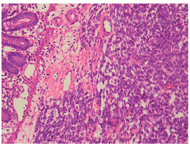

例1患者肿瘤细胞排列呈片状、索条样及网状,或形成交通状的血窦网,位于肠壁全层。瘤细胞呈上皮样,大小比较一致;核呈圆形、卵圆形或梭形,细胞核大、淡染;部分细胞核可见小核仁,异型性明显,核分裂像易见(图2,图3图4);间质伴灶片状出血。与2年前左大腿外侧及左侧腹股沟EA肿瘤组织学相似(图5)。

例2患者上皮样肿瘤细胞呈实性片状排列,位于黏膜下、肌层及浆膜层。瘤细胞呈圆形及卵圆形,核大淡然,异型性更明显;可见大红核仁,局部可见血窦及血管网结构;间质可见慢性炎细胞浸润(图6,图7图8)。与1年前左肺上叶EA肿瘤组织学结构类似(图9)。